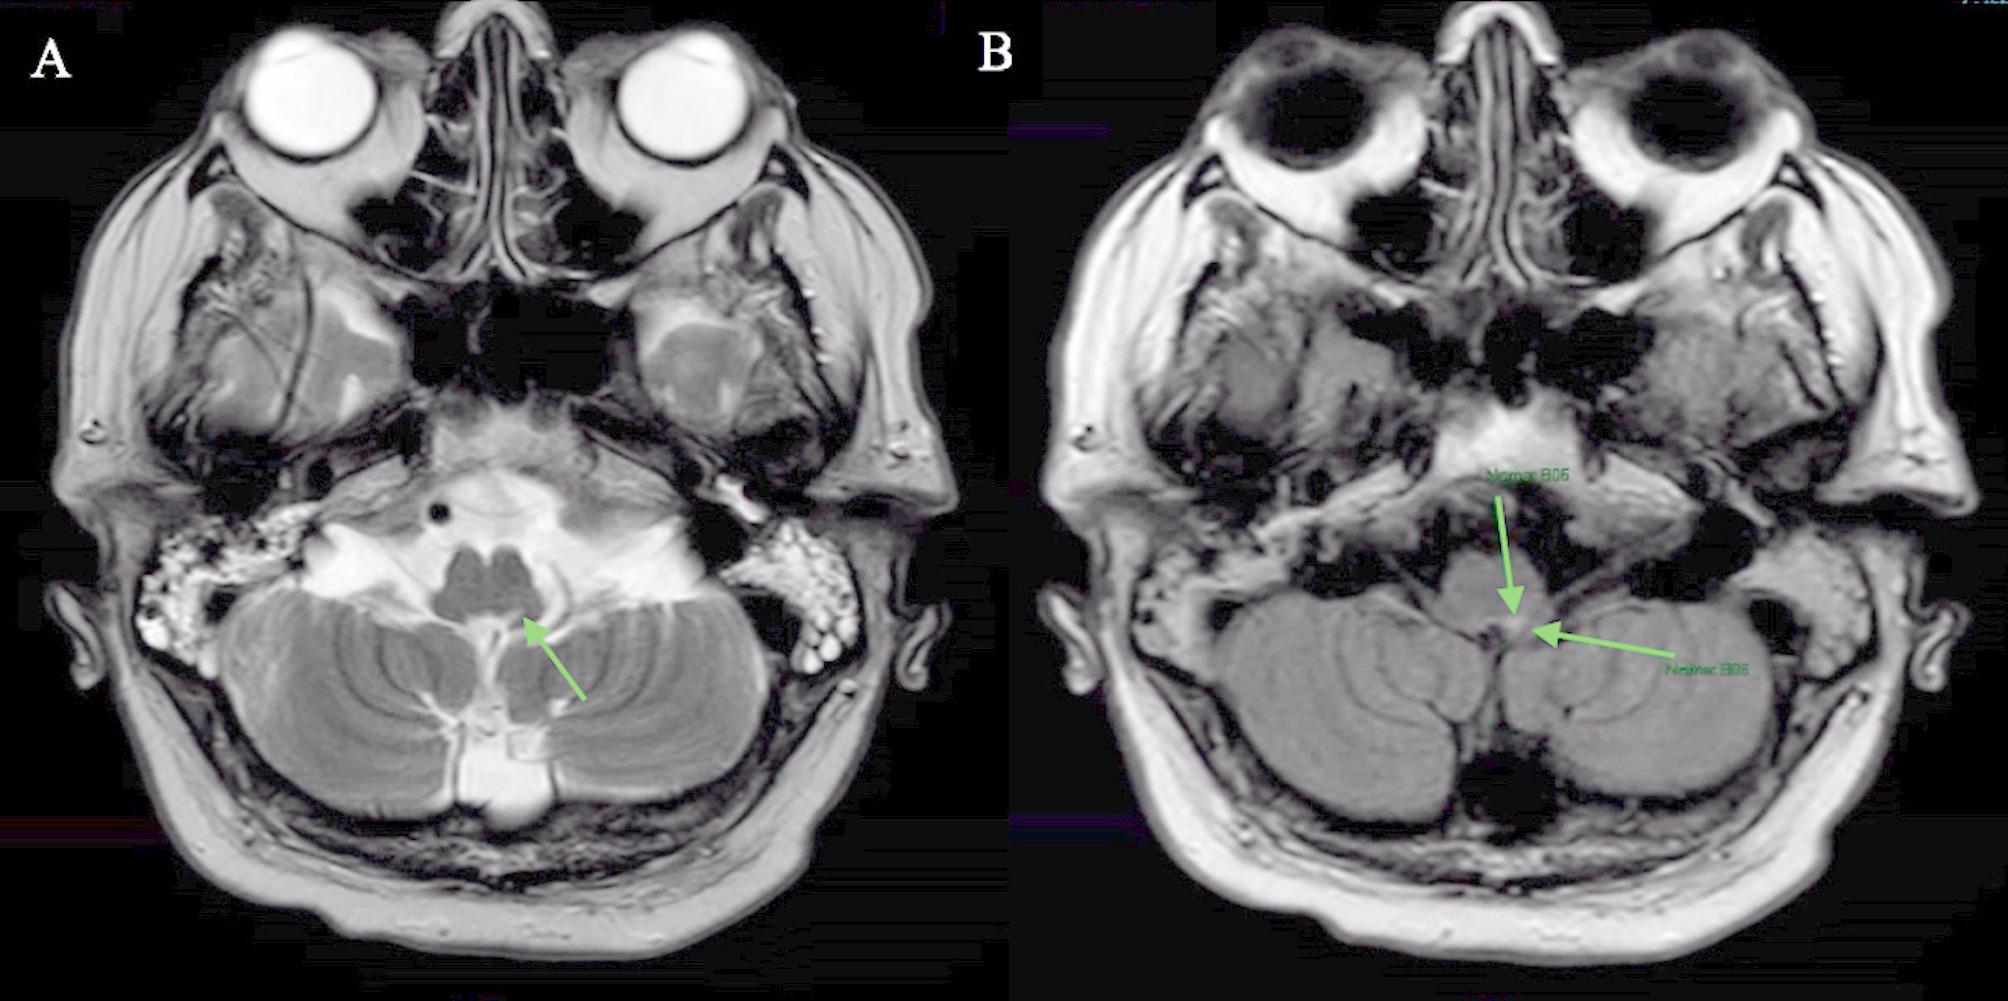

Clinical features: We describe the case of a 64-year-old previously healthy, immunocompetent man who presented with acute bulbar symptoms (difficulty swallowing, change in phonation, and drooling). His symptoms progressed in severity and he ultimately required intubation due to declining lung function and inability to manage his secretions. Clinical examination revealed bulbar dysfunction without involvement of other cranial nerves. A lumbar puncture revealed albuminocytological dissociation: elevated protein (9.8 g/L), nonerythroid cell count (13 cells/µL) with predominantly lymphocytic count. He received a five-day course of intravenous immunoglobulin for presumed Guillain-Barré syndrome. Initial magnetic resonance imaging (MRI) showed mild microangiopathic changes in the brain with no parenchymal, leptomeningeal, or cranial nerve enhancement. Cerebrospinal fluid (CSF) analysis was positive for varicella zoster virus (VZV). He was treated with intravenous Acyclovir 10 mg/kg three times daily for 14 days with no initial improvement and underwent a tracheostomy. Subsequent MRI was consistent with rhombencephalitis.